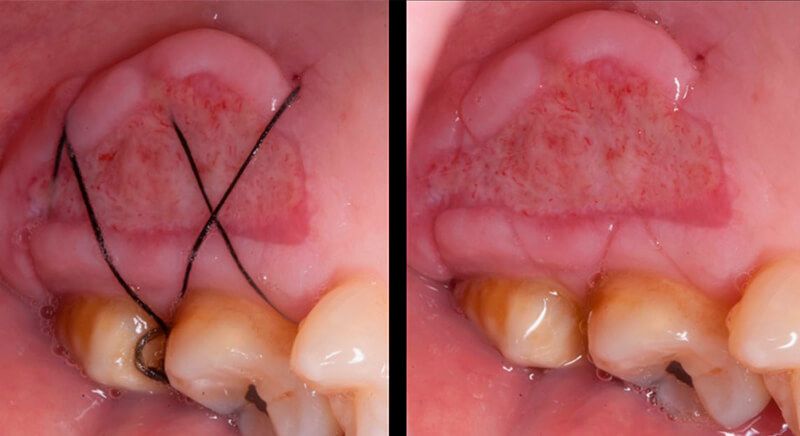

The tissue with epithelium was taken from the palate and de-epithelialized outside of the mouth. This obtains a lamina propria graft with better density and quality than if it were obtained with a single incision to the palate.